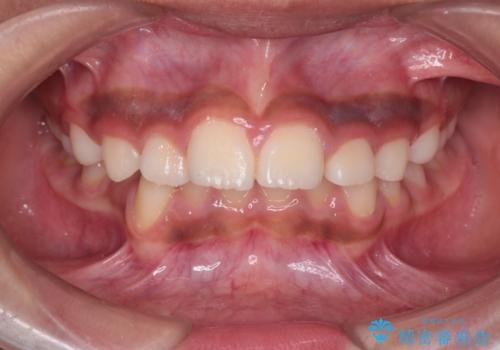

審美装置を用いたワイヤー矯正|非抜歯で歯の凸凹を改善

- 患者様は**歯の凸凹(叢生)**を気にされて来院されました。診査の結果、歯列のスペースが不足しているものの、抜歯をせずに改善できる状態でした。そこで、目立ちにくい審美装置(白いブラケットとホワイトワイヤー)を使用したワイヤー矯正を提案しました。歯列のアーチを広げながら、適宜IPR(歯の幅をわずかに調整する処置)を行い、非抜歯で自然な歯並びへと導く計画を立てました。

治療では、白いブラケットとホワイトワイヤーを使用し、矯正装置が目立ちにくいよう配慮しました。歯列を拡大しながら適切に歯を移動させ、IPRを併用することで、無理なくスペースを確保しました。見た目に配慮しながら、歯の凸凹をスムーズに整え、噛み合わせも改善。患者様からは「装置が思ったより目立たず、歯並びがきれいになって嬉しい」との声をいただきました。